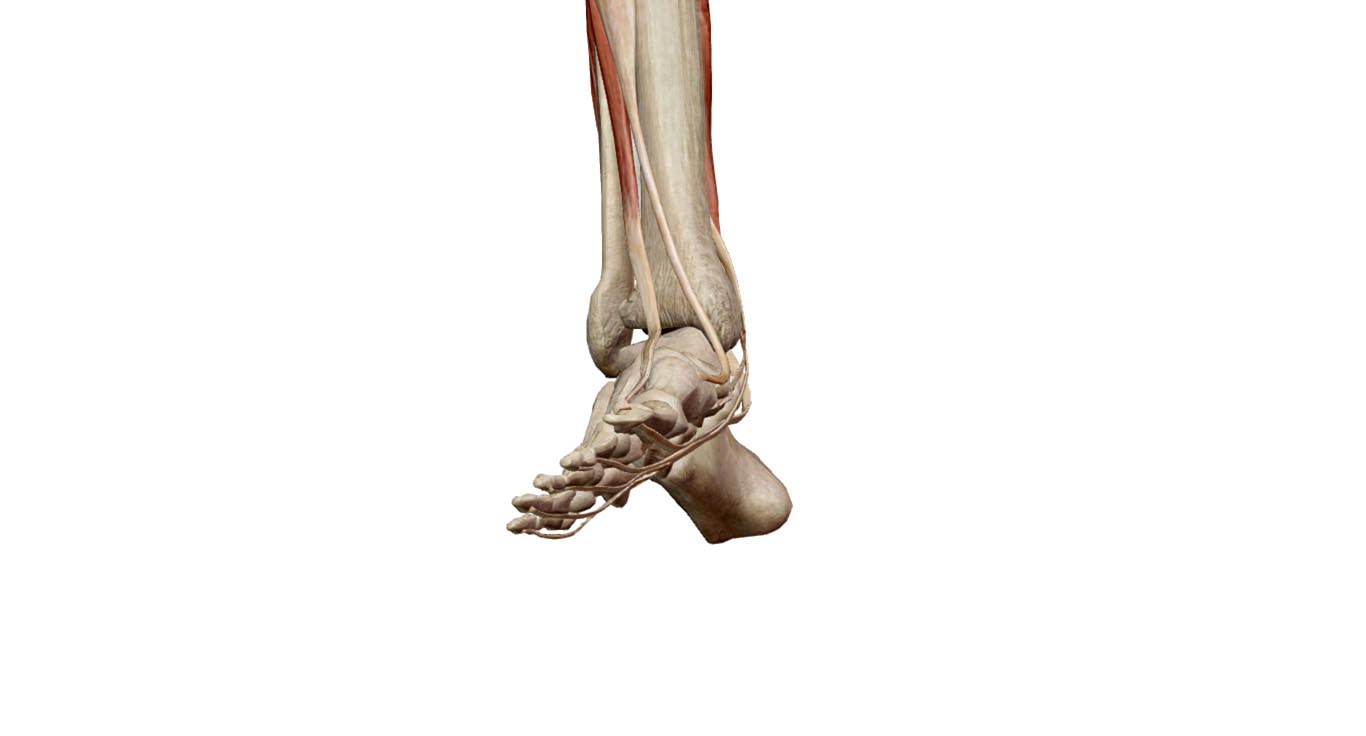

前脛骨筋は、脛骨前縁(いわゆる向こうずね)のすぐ外側に位置し、足関節の背屈と内反とを行う。背屈時には下腿前面で緊張した筋腹と太い腱を触れる。足を固定すると、下腿を前に傾ける。歩行時には背屈筋として重要で、足を前に出すときには足関節を背屈し、足先が地面をすらないようにする。(p.275 下腿前面の筋(伸筋群))

長母指伸筋

後脛骨筋・長指屈筋・長母指屈筋

後脛骨筋・長指屈筋・長母指屈筋の3屈筋は下腿後面の深層にあり、それらの腱は脛骨の内果の後側を回って足底に達する。内果と踵骨の間を橋渡しする屈筋支帯により、屈筋腱は保持される。

後脛骨筋は、足を強く内反する。また、縦足弓(足の縦アーチ)の内側部を高く保つ働きがある。

長母指屈筋は母指を屈曲させ、長指屈筋は第2~5指を屈曲させる。両筋とも足関節の底屈、内反に加わり、また縦足弓の維持を助ける。(p.277 下腿後面の筋(屈筋群))